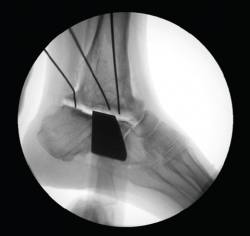

- Resección intraoperatoria (Figura 8).

- Diseño de la guía de corte guiada por aguja de Kirschner (Figura 12).

- Colocación de la guía intraoperatoria sobre relieves óseos (Figura 13).

- Resección intraoperatoria (Figura 14).